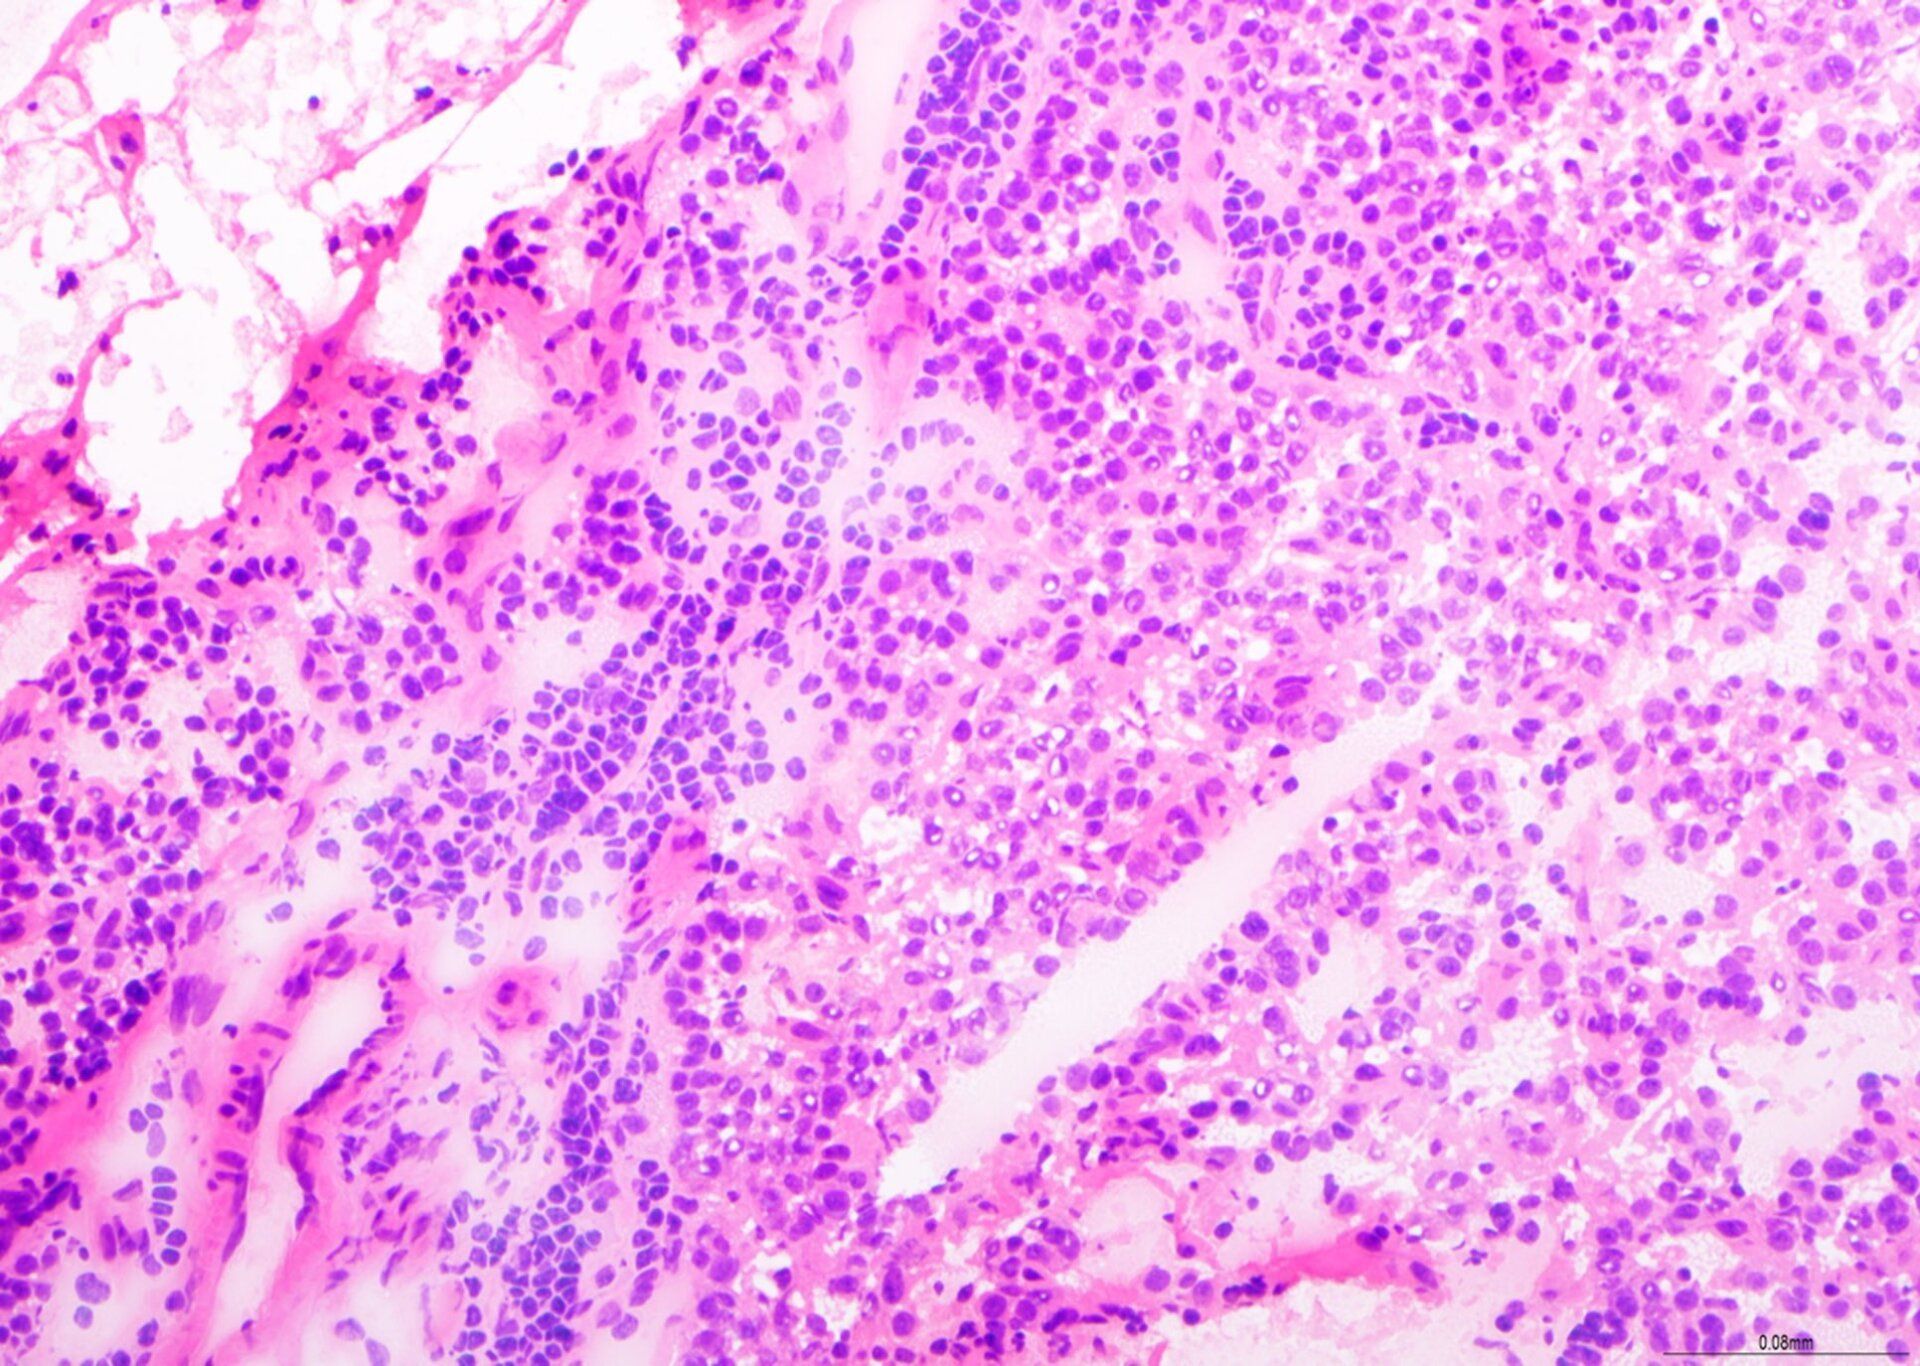

H&E - BMT-ordning

Dette er en fremragende forberedelse til en BMT-biopsi med afbalanceret H&E-farvning, god kromatindetaljering og selektiv farvning af celletyper i knoglemarvsvævet. Dette præparat blev scoret 9/10 ved vurdering.